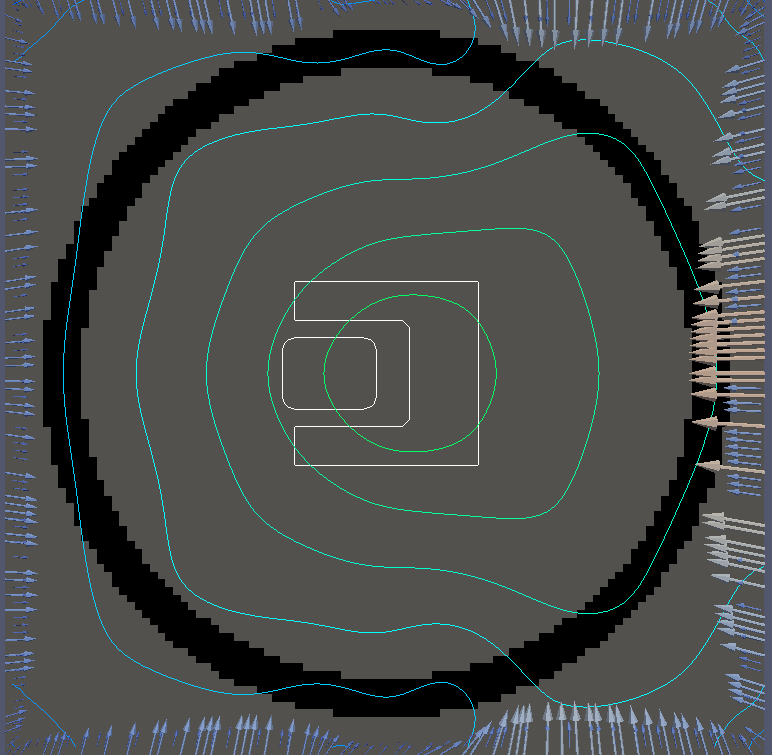

For testing, we use three tumor/risk region regions similar to those in [13]. Specifically, we define the regions in Table 3 and are shown in Figure 1; the void region is shown in black and the tumor and risk regions are traced in white. In the basic target case, seen in Figure 1(a), the tumor region is a box, as is the risk region. The second, intermediate target case, seen in Figure 1(b), involves an L-shaped tumor around a box-shaped risk region. Finally, the complex target case in Figure 1(c) involves a C-shaped tumor around a risk region.

Figure 2 shows the optimal boundary source term for both and The vectors shown on the boundary are the time-integrated values of normalized and then scaled by In Figures 2(a), 2(c), and 2(e) (corresponding to ), the isolines are spaced at intervals of the maximum of the desired dose (here, 5). In the intermediate and tracking cases, we see that relatively low dose levels are attained, primarily due to the high penalty to any dose deposited in the risk region. In Figures 2(b), 2(d), and 2(f)(corresponding to ), the isolines are spaced at intervals of of cells killed. Here a high proportion of the tumor cells are killed (in each case ) while in the Intermediate and Basic cases, the tumor has at least survival; in the Complex case, the risk region has survival.